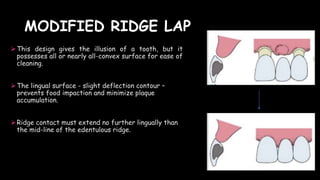

The document discusses pontic design for fixed dental prostheses. It covers pretreatment assessment of residual ridge contours, classifications of ridge deformities, surgical modification techniques, and ideal requirements for pontics. Pontic designs are classified based on their shape and materials. Factors in pontic selection include esthetics and oral hygiene. Common designs for anterior and posterior regions are described, including sanitary, ovate, and saddle pontics. Biological considerations for pontic design involve maintaining the residual ridge, abutment teeth, and supporting tissues.